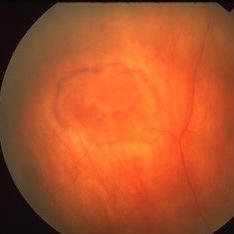

Guardian Angel

Dec 11 2024 by Virginia Gebhart

48 year old female 3 months s/p brachytherapy for choroidal melanoma. Persistent subretinal and increased subfoveal fluid. Will observe for now, will consider Ozurdex if no improvement. BCVA 20/80

Photographer: Virginia Gebhart, Retina Consultants of Carolina

Imaging device: Optos California

Condition/keywords: brachytherapy, demarcation line, fundus autofluorescence (FAF), serous detachment, subretinal fluid